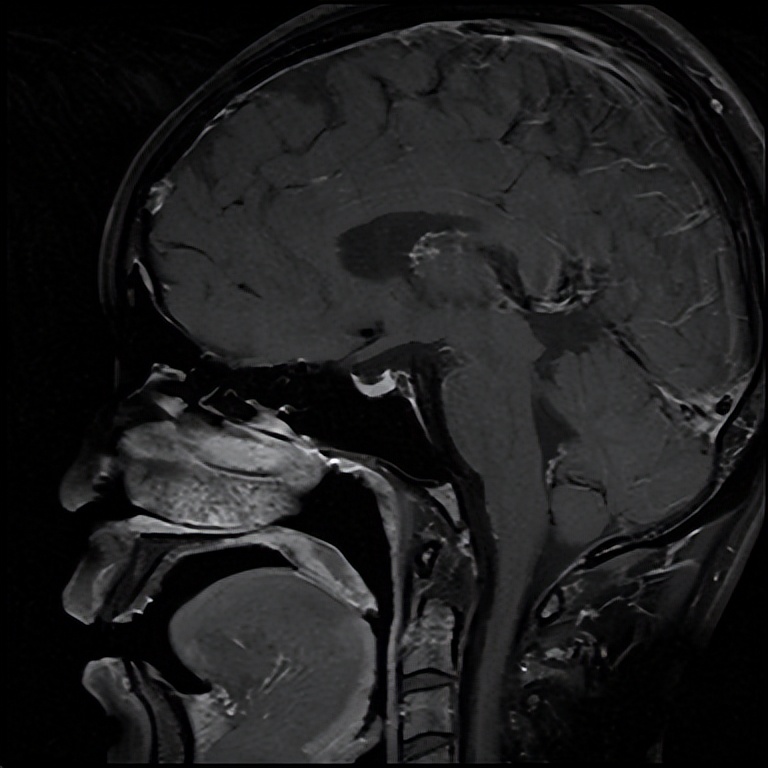

住院期间,银主任经过详细的询问病史和查体,为王女士有针对性地完善了相关检验、检查,入院急查血钠107.0mmol/L,血氯76.0mmol/L(参考范围96-108mmol/L),经积极补钠、护胃及对症支持治疗后王女士的血钠稳步上升,症状逐渐减轻,相关结果回报上午皮质醇、促肾上腺皮质激素(ACTH)水平降低,垂体磁共振未见明显异常。会不会是内分泌方面的因素导致低钠血症呢?深圳大学总医院内分泌代谢病科派驻罗城县人民医院内四科的丘雅维主治医师应邀会诊。丘医生分析患者体型消瘦,皮肤黏膜无明显色素沉着,低血压,轻度贫血,白细胞及中性粒细胞、血糖和糖化血红蛋白均偏低、低钠低氯、上午皮质醇和ACTH水平降低,初步考虑继发性肾上腺皮质功能减退可能性大,并对患者垂体磁共振再次阅片,发现垂体组织受压变扁,表现为部分性空泡蝶鞍。请深圳大学总医院影像科派驻罗城县人民医院影像科的杨智钧主治医师阅片后也支持部分性空泡蝶鞍的影像学诊断。

注:箭头所指为受压变扁的垂体。

那么什么叫空泡蝶鞍呢?所谓空泡蝶鞍综合征,是因鞍膈缺损或垂体萎缩,蛛网膜下腔在脑脊液压力下疝入鞍内,其中脑脊液填充,致蝶鞍扩大变形,垂体受压变平而产生的一系列临床变现,患者可出现头痛、视野缺损、垂体功能异常等表现。而垂体功能异常可显现为一种或多种垂体相关激素水平异常,如影响到肾上腺皮质轴导致肾上腺皮质功能减退,患者可出现头晕、血压降低、食欲减退、恶心呕吐、疲乏无力、消瘦、低血糖、低血钠等表现。